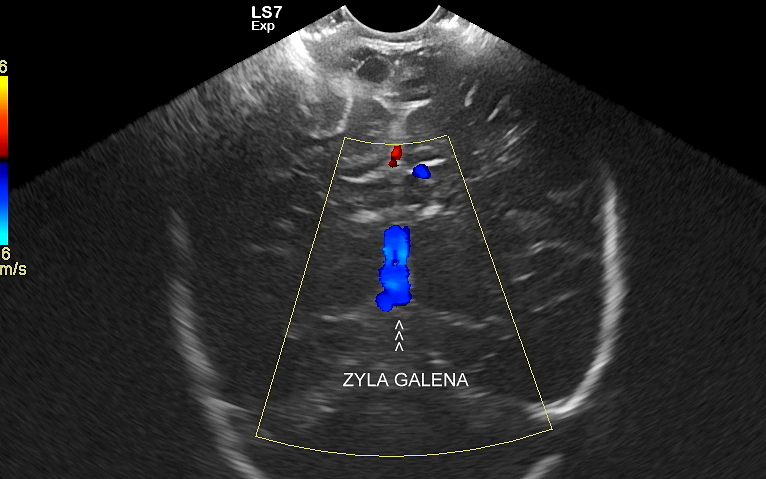

W USG główki dziecka oceniane są struktury wewnątrzczaszkowe, tj. mózg wraz z jego układem komór wewnętrznych, sploty naczyniówkowe, istota biała mózgu i obszary jąder podstawy mózgu, morfologia zakrętów i bruzd mózgowia, przestrzeń przymózgowa, a w trybach dopplerowskich wybrane naczynia tętnicze i żylne mózgu, w tym zatoki żylne. Oceniane są również cechy ciśnienia śródczaszkowego. W opisie badania podawane są również wymagane przez neurologa tzw. wskaźniki komorowe oraz wymiary wybranych struktur.

Jednocześnie dr Szczepański jako pierwszy we Wrocławiu wprowadzał do diagnostyki USG dzieci sprzęt wówczas najwyższej dostępnej klasy; w 2012 r. był to aparat GE Logiq 7 Expert, a w 2022 r. aparat z przełomową technologią Samsung V8. Należy również podkreślić, iż poza klasycznym USG przezciemiączkowym dr Szczepański wprowadził do regularnego zastosowania rozszerzone badanie USG główki z oceną szwów czaszkowych, z obrazowaniem naczyń wewnątrzmózgowych Dopplera oraz tkanek miękkich pokrywy czaszki.